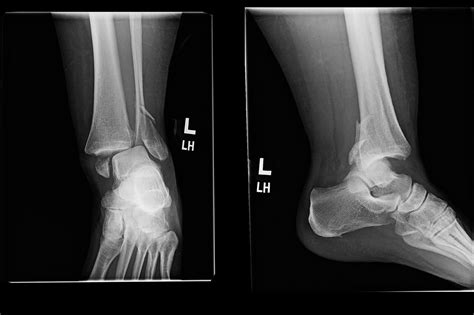

• Positioning: You will be asked to sit or lie down on an examination table. The technician will position your ankle in three standard views: an anterior-posterior (front), lateral (side), and a mortise view (a slightly rotated view that better visualizes the joint space).

Once the images are captured, they are reviewed by a radiologist. The broken ankle Xray will reveal whether there is a cortical breach—the medical term for a break in the bone's outer shell. The report will describe the type of fracture, which helps the orthopedic surgeon plan the treatment.

Hairline Fracture Small, thin crack in the bone. Cast or walking boot.

Displaced Fracture Bones are out of alignment. Reduction or surgery.

Comminuted Fracture Bone is shattered into pieces. Surgery (ORIF).

Avulsion Fracture Tendon/ligament pulls a piece of bone off. Variable (depending on size).